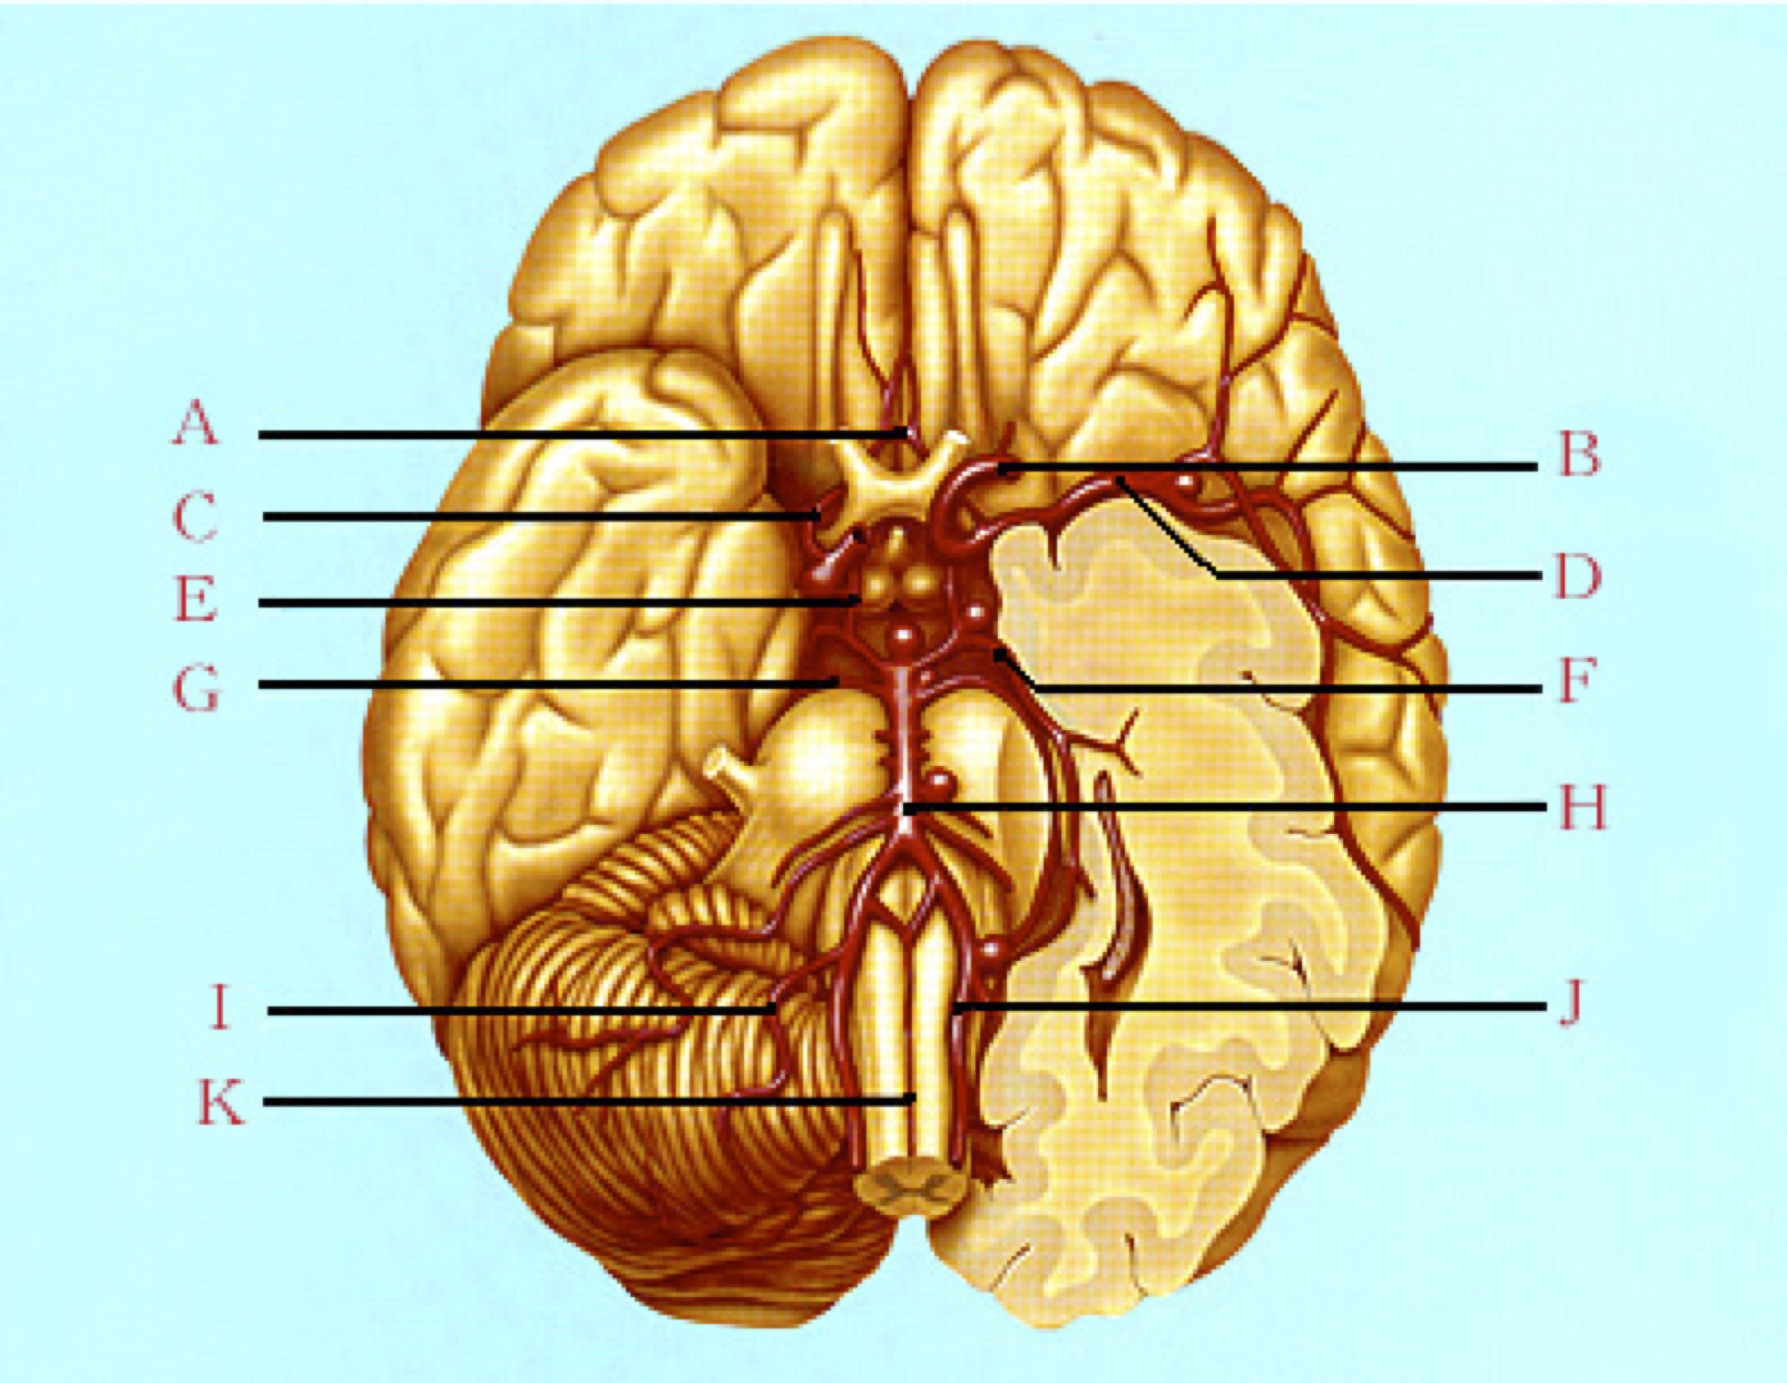

ウイリス動脈輪

A:前交通動脈

B:内頚動脈

C:前大脳動脈

D:中大脳動脈

E:後交通動脈

F:後大脳動脈

G:上小脳動脈

H:脳底動脈

I:後下小脳動脈

J:椎骨動脈

K:前脊椎動脈